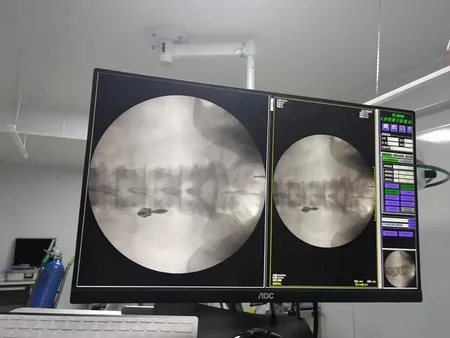

Gracias a su intensificador de imagen, este equipo de imagenología ofrece una visualización estable y de la mejor calidad, mientras reduce al mínimo la exposición a la radiación. Incorpora un generador de alto voltaje y tecnología de alta frecuencia que garantizan un rendimiento confiable incluso en los entornos quirúrgicos más exigentes. Su pantalla táctil LCD de 10.4 pulgadas es intuitiva, gira hasta 180° y está fabricada con materiales resistentes a la corrosión. Además, incluye un sistema de mensajes de error en chino lo que facilita la resolución de problemas para usuarios locales.

Inlcuye funciones avanzadas tales como fluoroscopía por pulsos y modo boost, para obtener imágenes claras y detalladas que permiten diagnósticos más seguros y procedimientos quirúrgicos más precisos. El diseño ergonómico incluye una manija para maniobras rápidas y una rueda con bloqueo de dirección que asegura estabilidad durante el uso. Su arco de 800 mm ofrece un amplio margen de movimiento para trabajar con mayor libertad. Además, cuenta con triple campo de imagen (9", 6", 4.5") para enfocar con precisión zonas específicas, una cámara CCD giratoria de 360° para una visión completa y rieles de guía lineal coreanos que facilitan un deslizamiento suave. Sus relés Omron contribuyen a reducir el ruido operativo y prolongan la vida útil del sistema.

El arco en C con intensificador de imagen es una herramienta clave en distintas áreas médicas y quirúrgicas. Gracias a su versatilidad, se emplea con frecuencia en quirófanos, salas de rayos X, áreas de urgencias y unidades especializadas en procedimientos vasculares e intervenciones mínimamente invasivas. Su utilidad abarca desde cirugías generales, ortopédicas y de columna, hasta intervenciones en urología, traumatología y cirugía torácica o abdominal. También es indispensable en procedimientos como la fijación de fracturas, estudios endoscópicos, angiografías discales y tratamientos vasculares como la angioplastia.